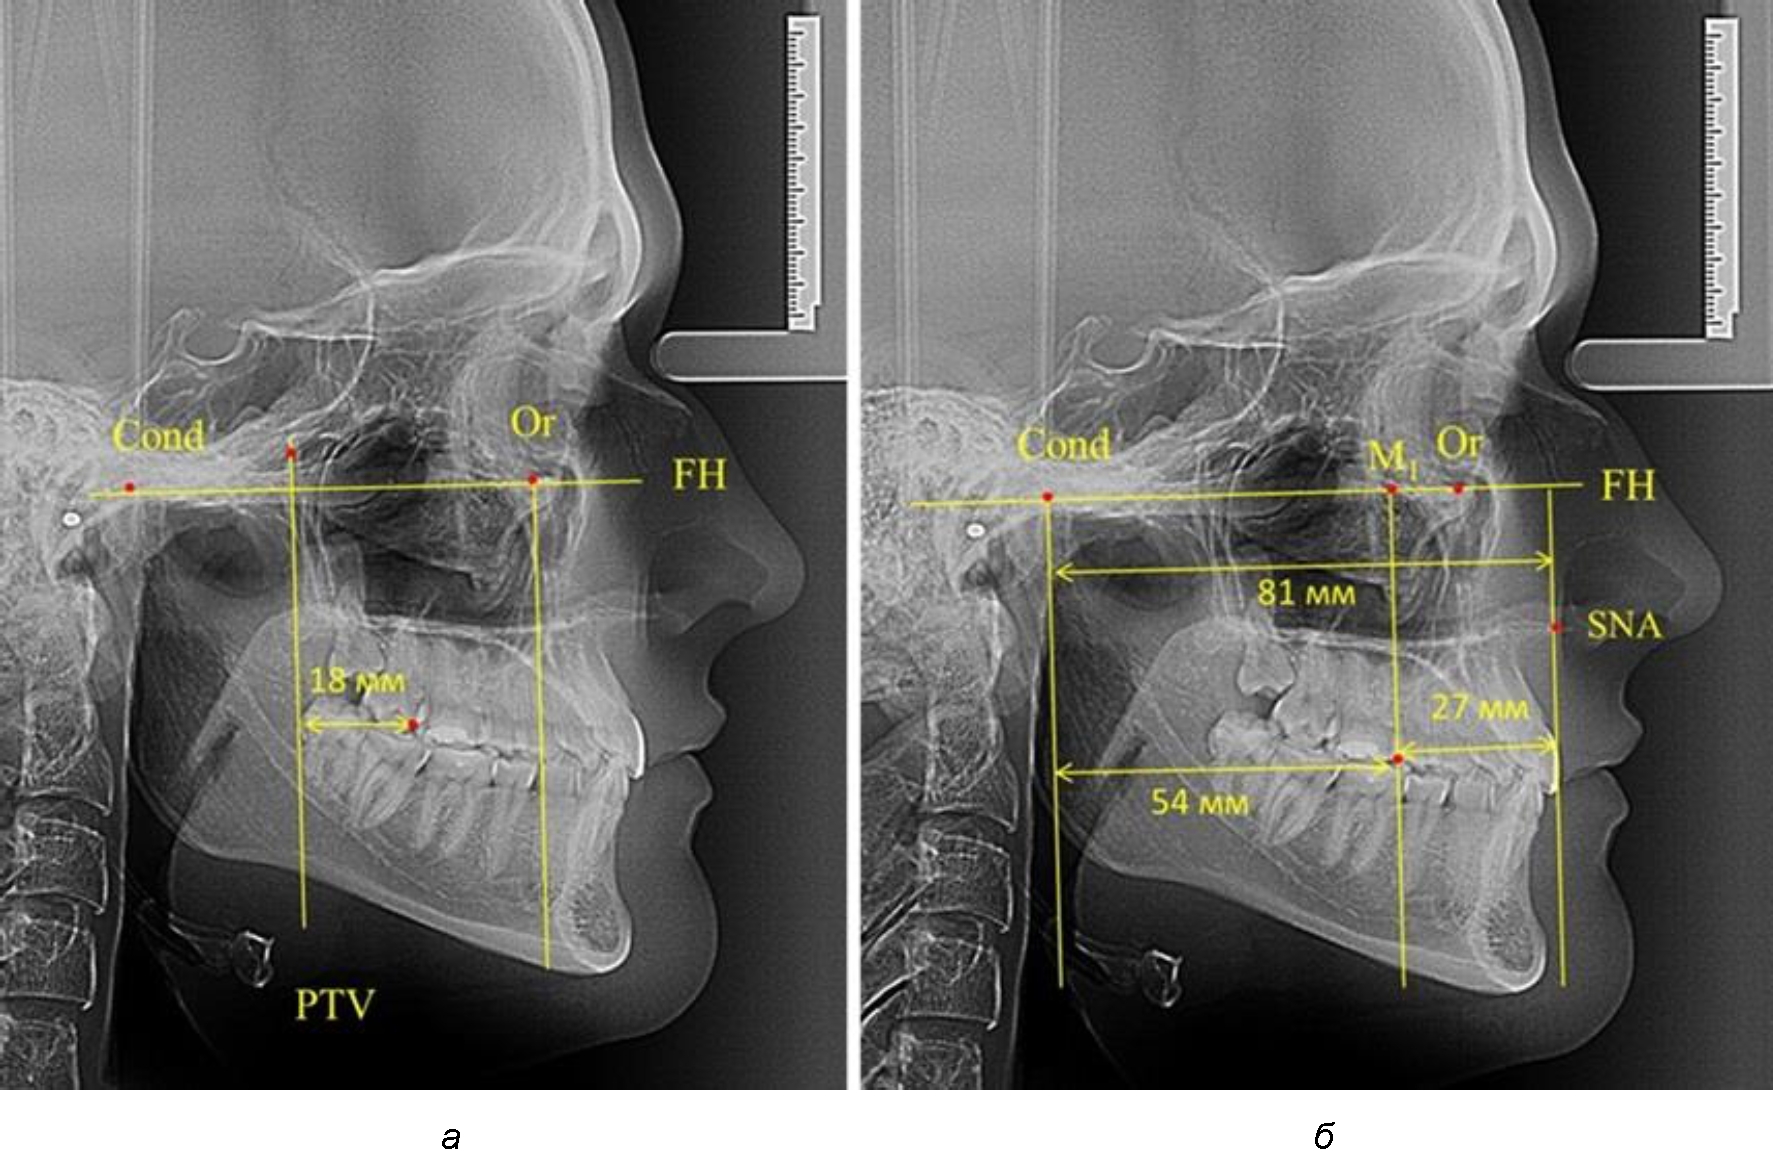

Согласно указанному методу на рентгенограммах проводили Франкфуртскую горизонталь. Учитывая мнения специалистов относительно ориентиров для построения и вариабельность положения наружного слухового прохода, в качестве задней точки использовали верхнюю выпуклость суставной головки нижней челюсти («Cond»). Передняя точка традиционно располагалась на нижнем крае глазницы и определялась как орбитальная точка Or.

Находили положение точки Pt, которая располагалась на пересечении нижнего края круглого отверстия и задней стенки крыловидно-верхнечелюстной щели, и перпендикулярно к Франкфуртской горизонтали проводили крыловидную вертикальную линию, которую принято обозначать как плоскость PTV. Расстояние от крыловидной вертикальной плоскости PTV до дистальной поверхности верхнего первого постоянного моляра определяло его положение, которое, по мнению R. E. McDonald, соответствовало возрасту пациента, увеличенному на 3 мм.

При проведении анализа к Франкфуртской горизонтали проводили передний и задний перпендикуляры. Передний спинальный перпендикуляр проходил через выступающую точку передней носовой ости (spina nasalis anterior – SNA), а задний суставной перпендикуляр опускали из кондилярной точки Cond. Молярный перпендикуляр проводили через медиальную поверхность первого постоянного моляра. Указанная вертикаль отделяла замещающие зубы постоянного прикуса от добавочных зубов (постоянных моляров), что вполне логично для анализа положения первых постоянных моляров в гнатическом комплексе (рис. 1).

Рис. 1. Метод определения положения первых верхних моляров по Ralph E. McDonald (а) и по предложенному методу (б)

Анализ проведенного исследования рентгенограмм показал существенную вариабельность практически всех линейных показателей. У молодых людей с физиологическим прикусом постоянных зубов расстояние от крыловидной вертикальной плоскости PTV до дистальной поверхности верхнего первого постоянного моляра в целом по группе составляло (18,37 ± 3,62) мм. Обращает на себя внимание большая ошибка репрезентативности из-за разницы между максимальными и минимальными значениями.

Среди анализируемых рентгенограмм минимальное значение расстояния по методу R. E. McDonald было 12 мм, а максимальное достигало 25 мм, что, по нашему мнению, обусловлено вариабельностью сагиттального размера гнатического отдела лица.